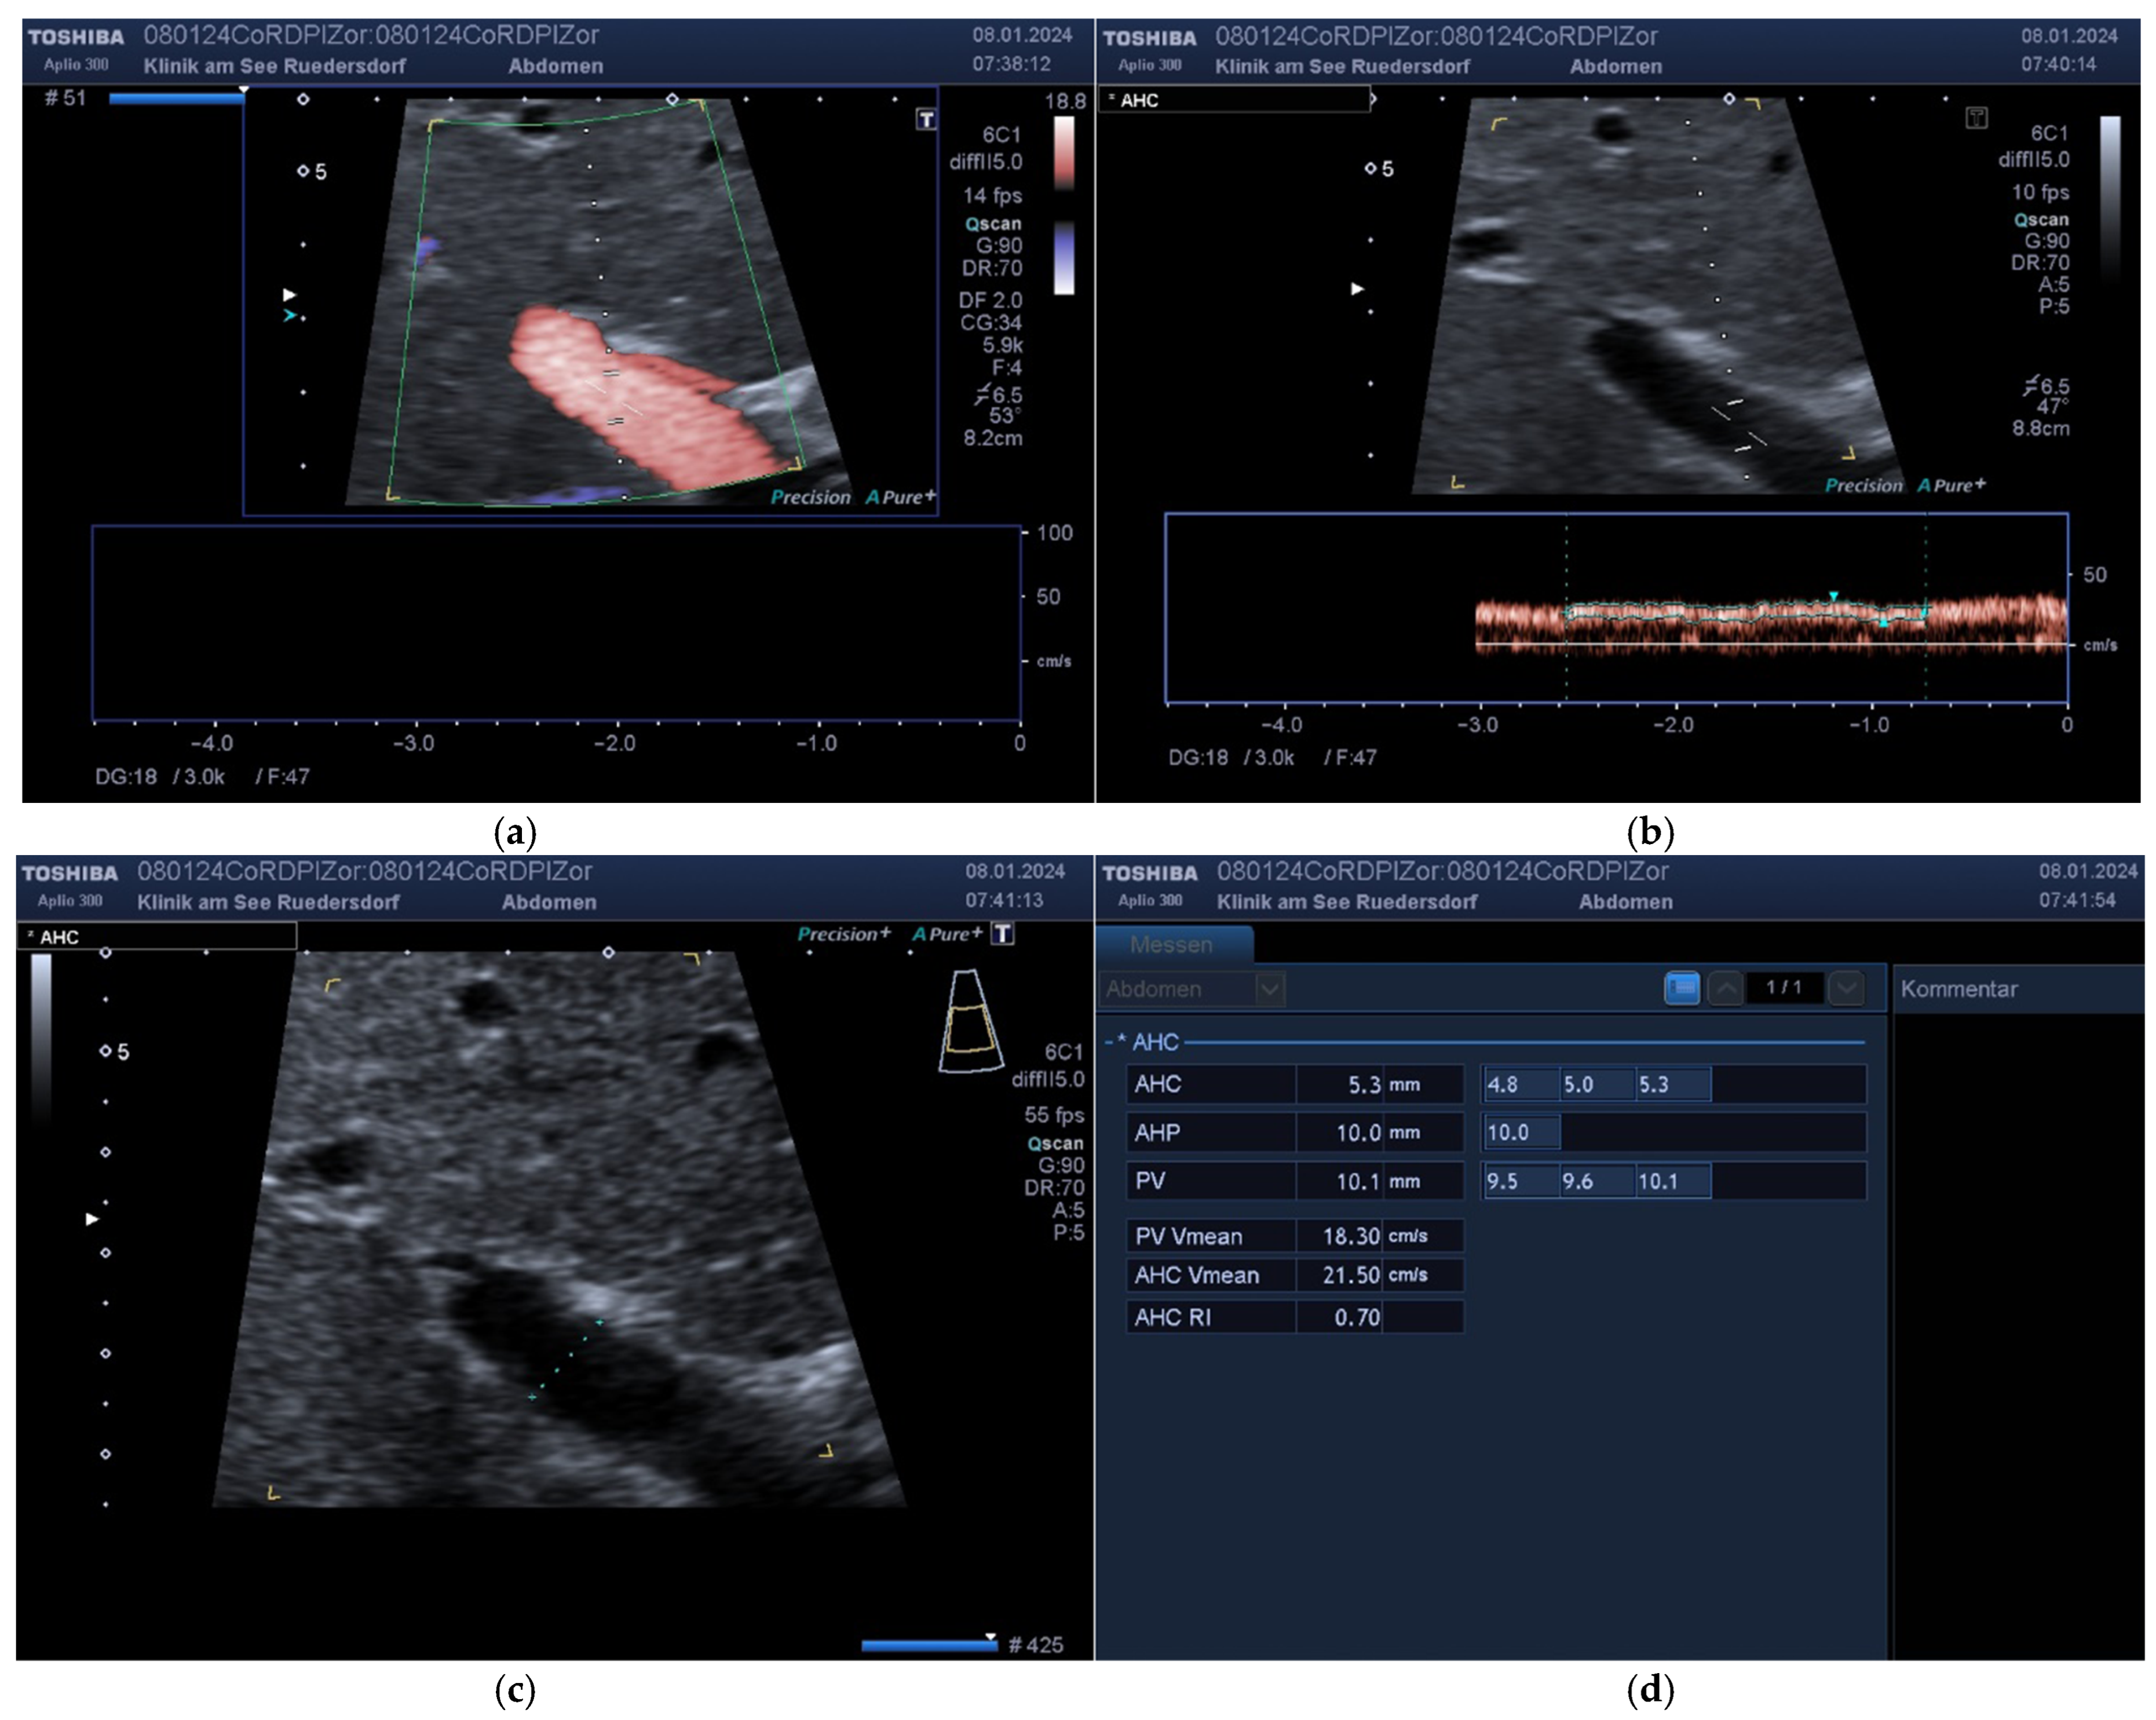

3.2. Measured Values and Calculated Blood Flow

| Mean D1 (SD) | 5.7 (1) | 52.1 (9.2) | 22.1 (7.3) | 579 (240) | 0.4 (0.1) |

| Mean D3 (SD) | 5.8 (0.9) | 48.4 (11.4) | 23.8 (8.1) | 598 (252) | 0.4 (0.1) |

| Mean tot (SD) | 5.7 (0.9) | 50.2 (10.5) | 23 (7.7) | 588 (245) | 0.4 (0.1) |

| Mean Diff (SD) | 0.0 (0.4) | −3.7 (10) | 1.7 (5.7) | 20 (148) | 0.01 (0.06) |

| p(Bias) | 0.50 | 0.002 | 0.008 | 0.30 | 0.55 |

| p(Var) | 0.97 | 0.29 | 0.73 | 0.70 | 0.82 |

| PCC | 0.91 | 0.54 | 0.73 | 0.82 | 0.87 |

| ICC (95% CI) | 0.91 (0.86; 0.94) | 0.51 (0.24; 0.67) | 0.71 (0.55; 0.82) | 0.82 (0.72; 0.89) | 0.87 (0.79; 0.92) |

| MVC | 0.04 | 0.13 | 0.13 | 0.14 | 0.07 |

| B/A Limits | (−0.78; 0.82) | (−23.3; 16.0) | (−9.4; 12.9) | (−270; 310) | (−0.13; 0.12) |